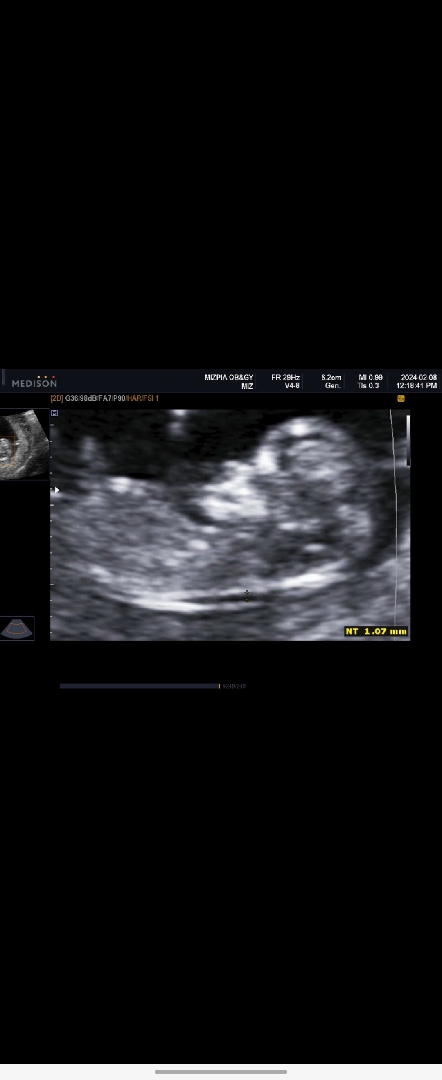

1차기형아검사하고와써영!!!!

신기한 입체초음파도보고 기형아검사두 하고왔는데 너무 정상으로 잘크고있다고 하셔서 맘이조금 놓이긴하네요 ㅎㅎ목투명대 1.07이면 너무걱정할 슈치는 아니게쬬~¿¿ㅎㅎ